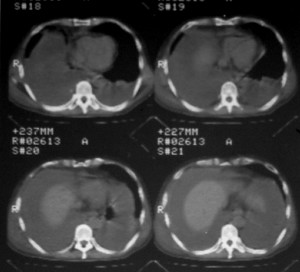

右侧肺癌术后:肝内可见多个大小不等的低密度结节影。腹腔及双侧胸腔大量积液。考虑:肺癌并胸膜及肝脏转移。

腹水,肝及右肾多发低密度影。考虑转移。

肝及右肾转移瘤,双侧胸水

右肾及肝内多发转移瘤,胸水。

1、右肺癌术后改变。2、双侧胸水、腹水。3、多发性肝囊肿,右侧肾囊肿。